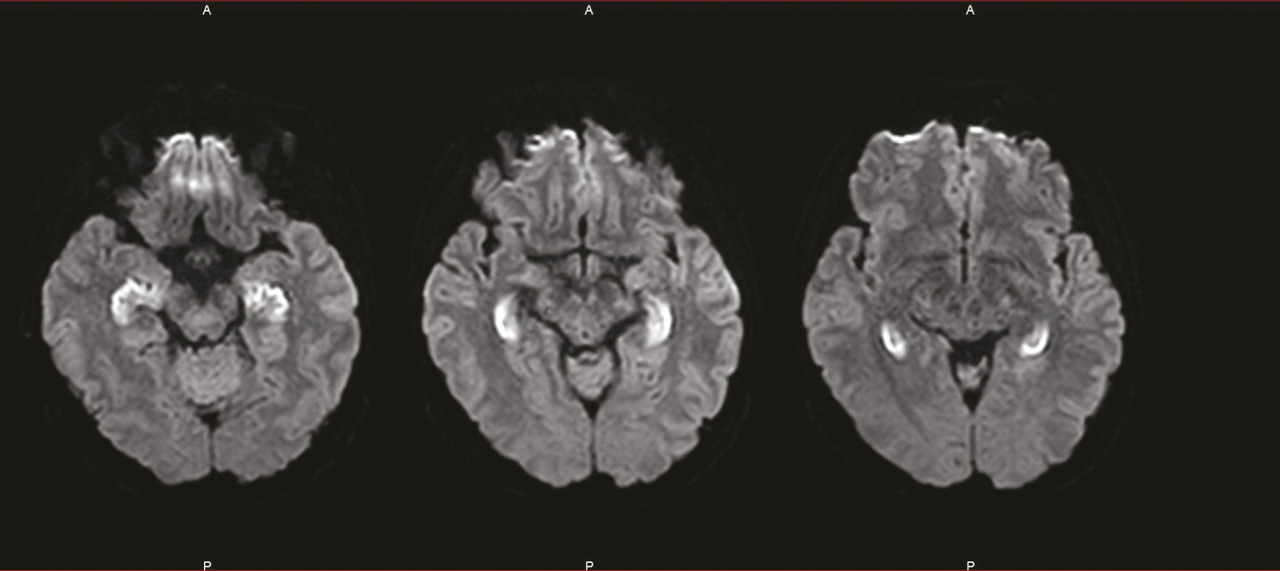

Les plus fréquentes sont les encéphalites dysimmunitaires, qu’elles soient paranéoplasiques ou non, dont le cadre ne cesse de s’enrichir avec la découverte d’anticorps antineuronaux ou anti neuropile. L’installation du tableau est souvent subaiguë. Les séquelles sont d’autant plus importantes qu’il y a eu un retard diagnostique et thérapeutique (fig. 2 ).

Les plus fréquentes sont les encéphalites dysimmunitaires, qu’elles soient paranéoplasiques ou non, dont le cadre ne cesse de s’enrichir avec la découverte d’anticorps antineuronaux ou anti neuropile. L’installation du tableau est souvent subaiguë. Les séquelles sont d’autant plus importantes qu’il y a eu un retard diagnostique et thérapeutique (